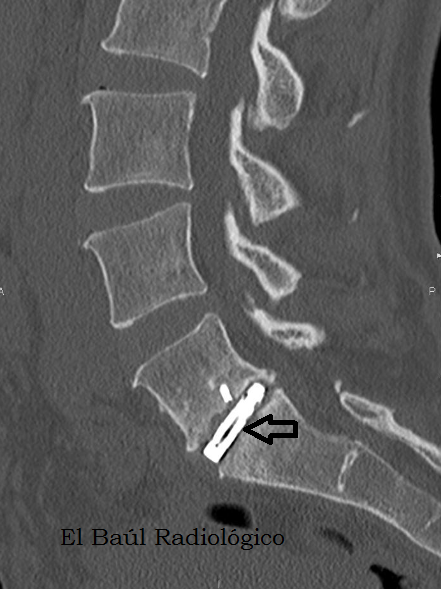

Protesis+intersom%C3%A1tica+4.png

FIGURA3) Implante intersomático en una imagen de TC, visto con ventana de partes blandas.

(An intersomatic implant in a CT image, seen with soft tissue window)

FIGURA 4) Implante intersomático en una imagen de TC, visto con ventana de hueso.

(An intersomatic implant in a CT image, seen with bone window)